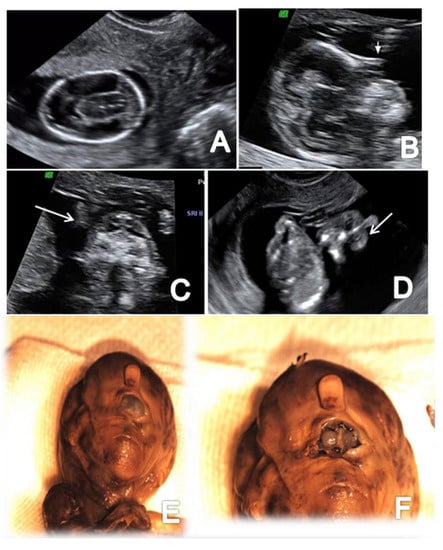

Figure 7.

A case of alobar holoprosencephaly diagnosed at 12 weeks + 5 days (Case 9): (A) transverse view of the abnormal brain cavities; (B) sagittal view of the fetal head showing proboscis (arrow); (C) frontal view of the fetal face showing extreme hypotelorism (arrow); (D) frontal view of proboscis (arrow); (E,F) specimen presentation aspect after medical TOP confirming proboscis and hypertelorism.